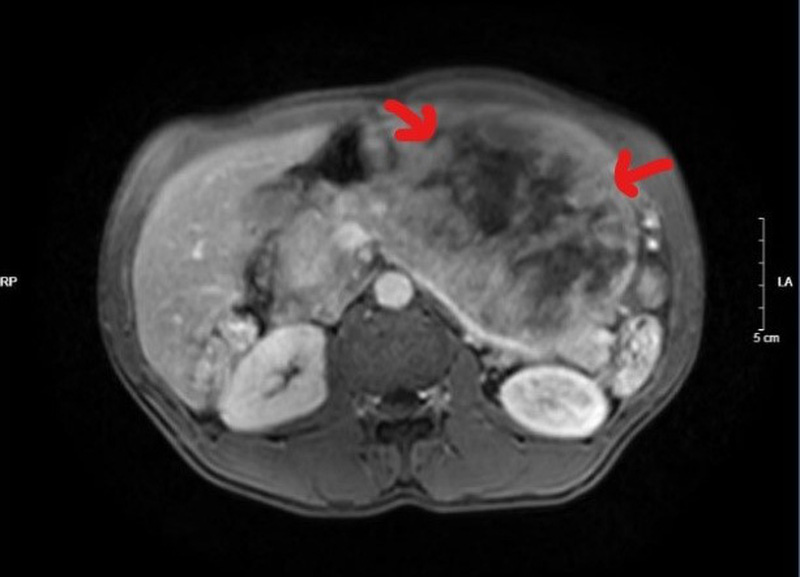

Khối u nặng gần 5kg của bệnh nhân. Ảnh: BVCC

Sau 3 tiếng tập trung cao độ, ê-kíp phẫu thuật đã cắt được khối u khổng lồ đường kính hơn 30cm, nặng 5kg cùng gần như toàn bộ dạ dày của bệnh nhân mà không làm tổn thương đến các tạng xung quanh.